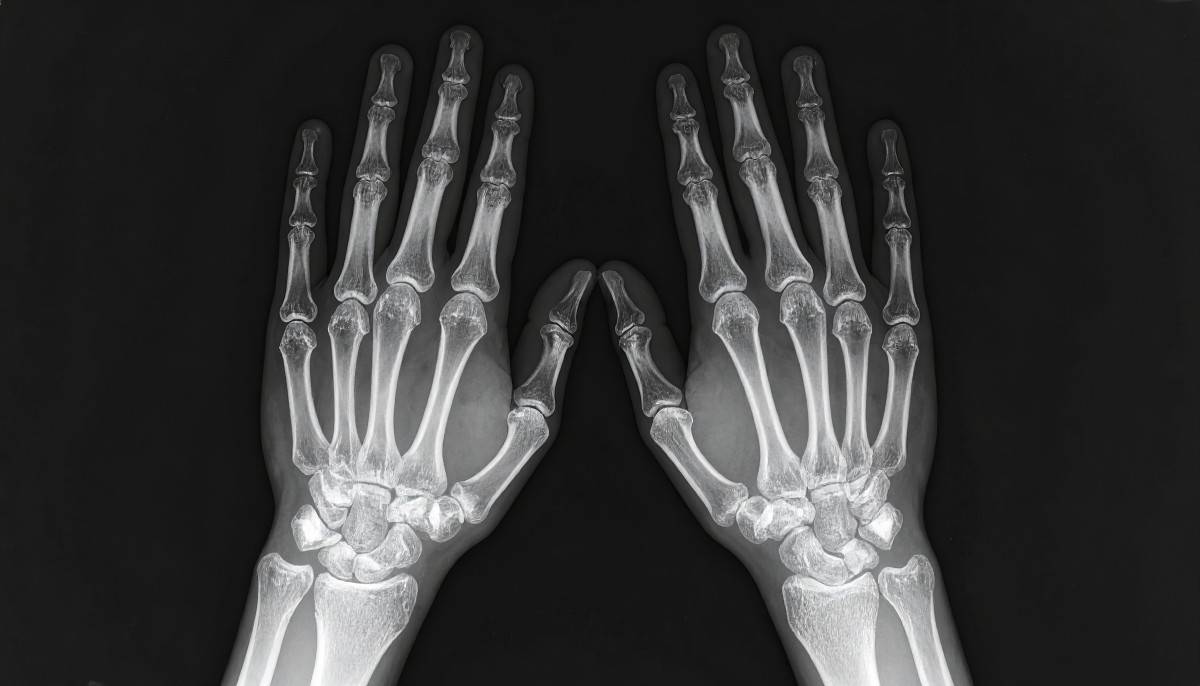

İltihaplı romatizmalarda tanının tek bir testle konulmadığını belirten Ertürk, genellikle üç temel değerlendirme yapıldığını ifade etti. Ertürk, “Tanıda amaç sadece hastalığın adını koymak değil; tipini, aktivitesini ve hasar riskini belirleyip tedaviyi kişiye özel planlamaktır. Özellikle 6 haftadan uzun süren eklem şişliği ve sabah tutukluğu varsa, erken romatoloji değerlendirmesi eklem hasarını önlemede çok kıymetlidir. Tanı sürecinde hastamızın şikâyetlerini ayrıntılı şekilde dinliyoruz. Ağrının süresi, sabah tutukluğu olup olmadığı, gece artan ağrı, aile öyküsü ve eşlik eden döküntü ya da göz şikâyetlerini değerlendiriyoruz. Fizik muayenede ise eklemleri, omurgayı ve ilgili sistemleri kapsamlı biçimde inceliyoruz. Gerekli gördüğümüz durumlarda kan testleri, görüntüleme yöntemleri ve bazı özel incelemelere başvuruyoruz. Kan testlerinde CRP ve sedimentasyon gibi iltihap göstergelerini, tam kan sayımını ve biyokimyasal testleri değerlendiriyoruz. Bazı hastalıklarda tanıyı desteklemek amacıyla özel antikor testleri ve genetik testler de isteyebiliyoruz. Görüntüleme aşamasında röntgen, ultrason ve gerektiğinde MR kullanıyoruz. Eklemde belirgin şişlik ve sıvı birikimi olan bazı durumlarda ise eklem sıvısını alarak enfeksiyon, gut gibi kristal hastalıkları ya da iltihap derecesi açısından inceleme yapıyoruz.” dedi